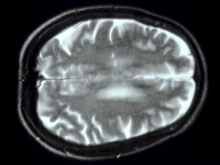

Как правило, этот недуг развивается вследствие осложнений во время родов, асфиксии или травмы головы. В любом случае, все дело в повреждении мозга, отмечает The Globe and Mail. О генетике врачи до недавнего времени говорили редко.

Но доктор Стэфан Шерер все изменил. Он провел исследование генов 115 детей с церебральным параличом. Также учитывался генетический профиль родителей. Оказалось, почти 10% детей имели большие хромосомные аномалии. Из них 70% не разделяли эти аномалии со своими родителями. Генетики были в шоке, когда увидели результаты.

Известно: в ходе работы эксперт фокусировался на одной генетической аномалии - вариации числа копий гена. Это большие части ДНК, которых или не хватает, или они скопированы. Человеку от родителей достаются две копии генов. Если одной копии нет или она удвоена (1 или 3 гена вместо нормальных 2), то развивается аномалия.

Какие именно гены, затронутые аномалией, стоят за развитием церебрального паралича, пока не установлено. Но в перспективе они точно будут найдены, уверен доктор. Это позволит проводить генетический скрининг еще до рождения ребенка.